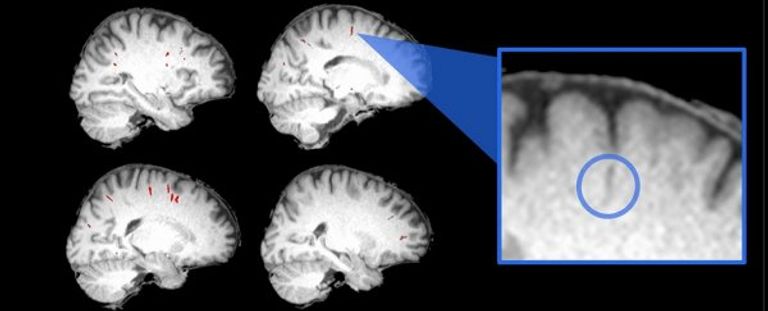

ورغم أن هذه التغيرات دقيقة للغاية، لا تتجاوز بضعة مليمترات، فإنها تتركز بشكل أساسي في مناطق الدماغ المسؤولة عن التوازن، وإدراك وضعية الجسم، والتحكم الحسي الحركي، وهي وظائف ضرورية للحركة الطبيعية تحت تأثير الجاذبية الأرضية.

وأظهرت التحليلات أن الدماغ لا يتحرك ككتلة واحدة فقط، بل يتغير شكله أيضا، إذ تتحرك مناطق مختلفة في اتجاهات متباينة. وكانت التغيرات أكثر وضوحا لدى رواد الفضاء الذين أمضوا عاما كاملا في الفضاء، حيث وصل التغير في بعض المناطق إلى ما بين 2 و3 مليمترات.

ورغم ذلك، لم تربط الدراسة هذه التغيرات بأي تأثيرات على الشخصية أو الذكاء أو القدرات الإدراكية. لكن التأثير الأكبر ظهر في منطقة "الجزيرة الخلفية" من الدماغ، وهي المسؤولة عن معالجة التوازن. وارتبطت التغيرات الأكبر في هذه المنطقة بضعف التوازن بعد العودة إلى الأرض، وهو ما يشتكي منه العديد من رواد الفضاء لأيام أو أسابيع، مع استمرار تعافٍ حسي حركي دقيق لأشهر لاحقة.